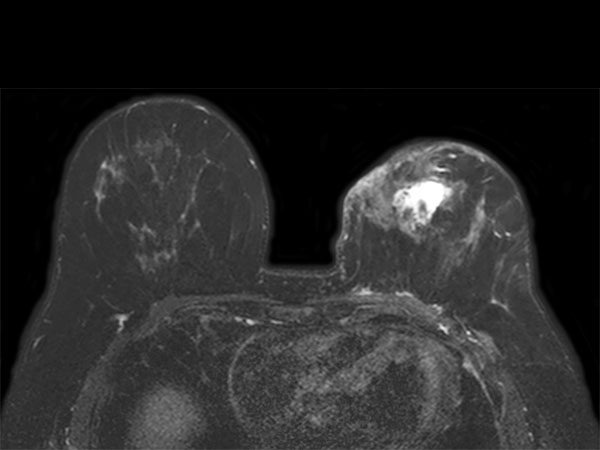

Dynamic axial eTHRIVE

-